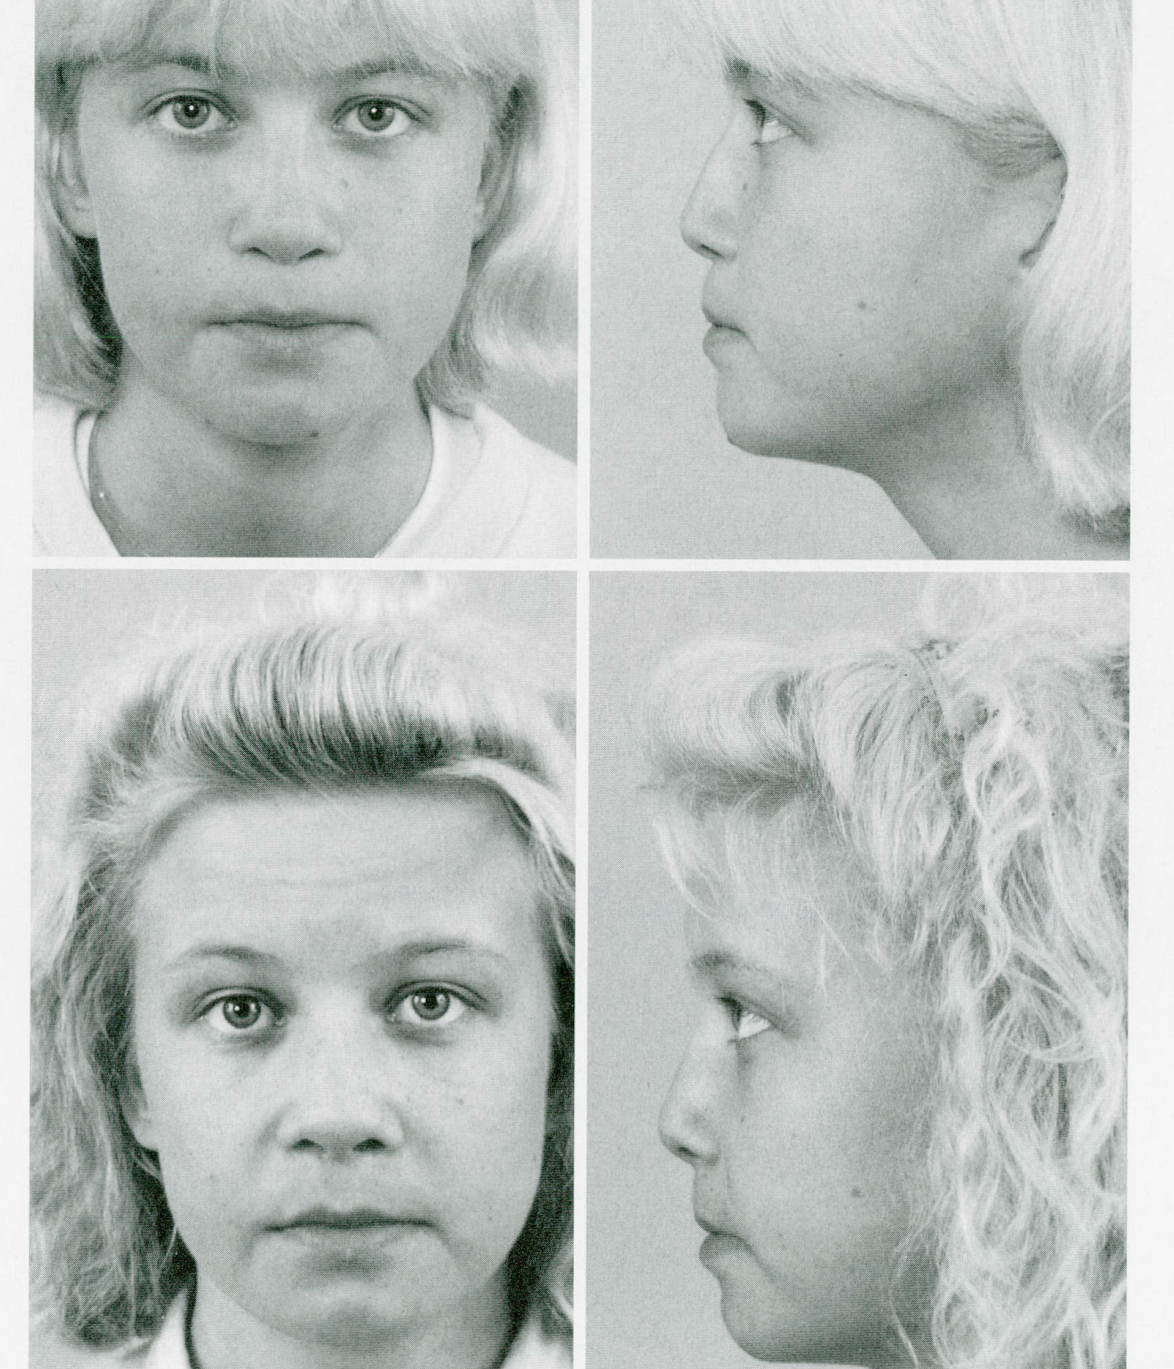

3. When LF 2 actually helps

- Lefort 2 only makes sense if your midface is severely recessed because you lack anterior facial depth caused by actuall maxillary retrusion rather than the paranasal / ANS area being recessed. A lefort 2 even avoids the ANS by cutting around it, so it would't fix the underlying cause of the recession. This might be why the patient who got a lefort 2 by giant had it segmented such that his ANS was rotated and advanced.

- The case below fits the criteria, the patients ANS and nose was fine in proportion to the rest of the face, but the maxilla sat almost vertical with little to none anterior facial depth. Advancing the lefort 2 block gave the missing anterior depth and transformed her frontal view.

Many "sunken" midfaces are caused more by a recessed ANS and paranasal area than by full maxillary retrusion. A correction of the paranasal region with an implant, graft, or a USO can often improve nasal projection, philtrum support, and overall facial harmony without needing extreme midface advancement. Lefort 2 should be used for severe anterior midface deficiency, not as a default when someone has midface retrusion.